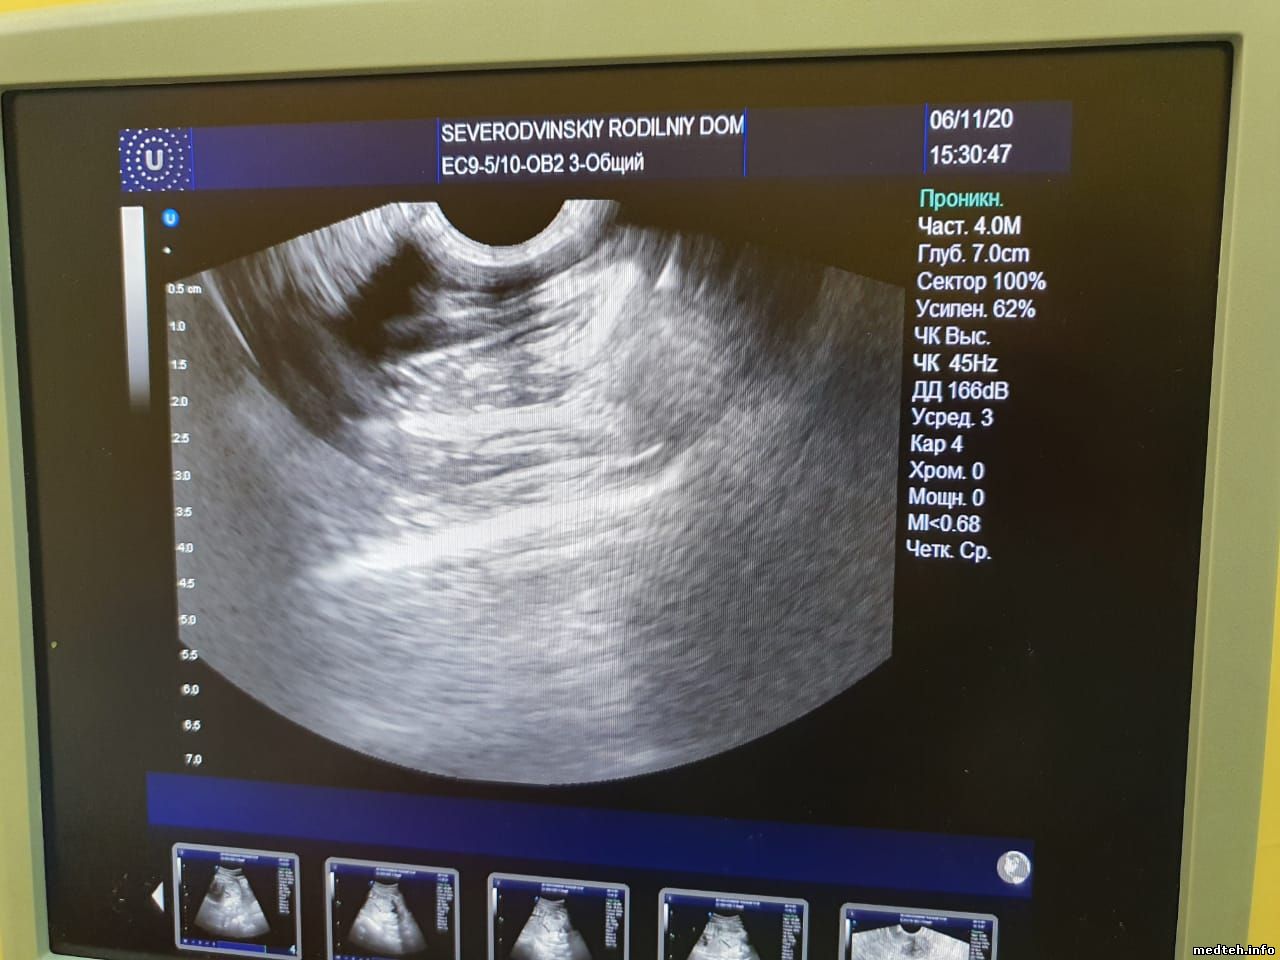

Подскажите, пожалуйста, в чем может быть проблема с датчиком?

На изображении сверху заметен сектор темнее остальных, создающий своего рода "тень", врачам мешает. При движении металлического предмета по поверхности линзы сектор в этом месте не исчезает, но тускнеет(менее яркий,чем в других частях сектора). Датчик вагинальный. С краю имеется небольшое повреждение линзы. В этом месте дефекта на изображении нет.

5377470.jpg (120.8 Kb) · 4425392.jpg (114.1 Kb) · 4316324.jpg (72.2 Kb) · 5838587.jpg (119.7 Kb)

Не уходит. В данном случае, наверное, было необязательно водить каким-то предметом. А вообще, чтобы проверить ПК. Если "выбиты", то в этом месте на секторе будет "провал". Разве нет? ...

9643944.jpg (24.5 Kb) · 9487175.jpg (89.1 Kb)

Похоже, что у вас есть повреждение ПК, но возможно, что может проблема в разъёме.

Если пару ПК у вас неисправны, то как раз примерно такое поле будет невидным.

Сектор выпадает, когда есть повреждение нескольких рядом (по моему опыту).